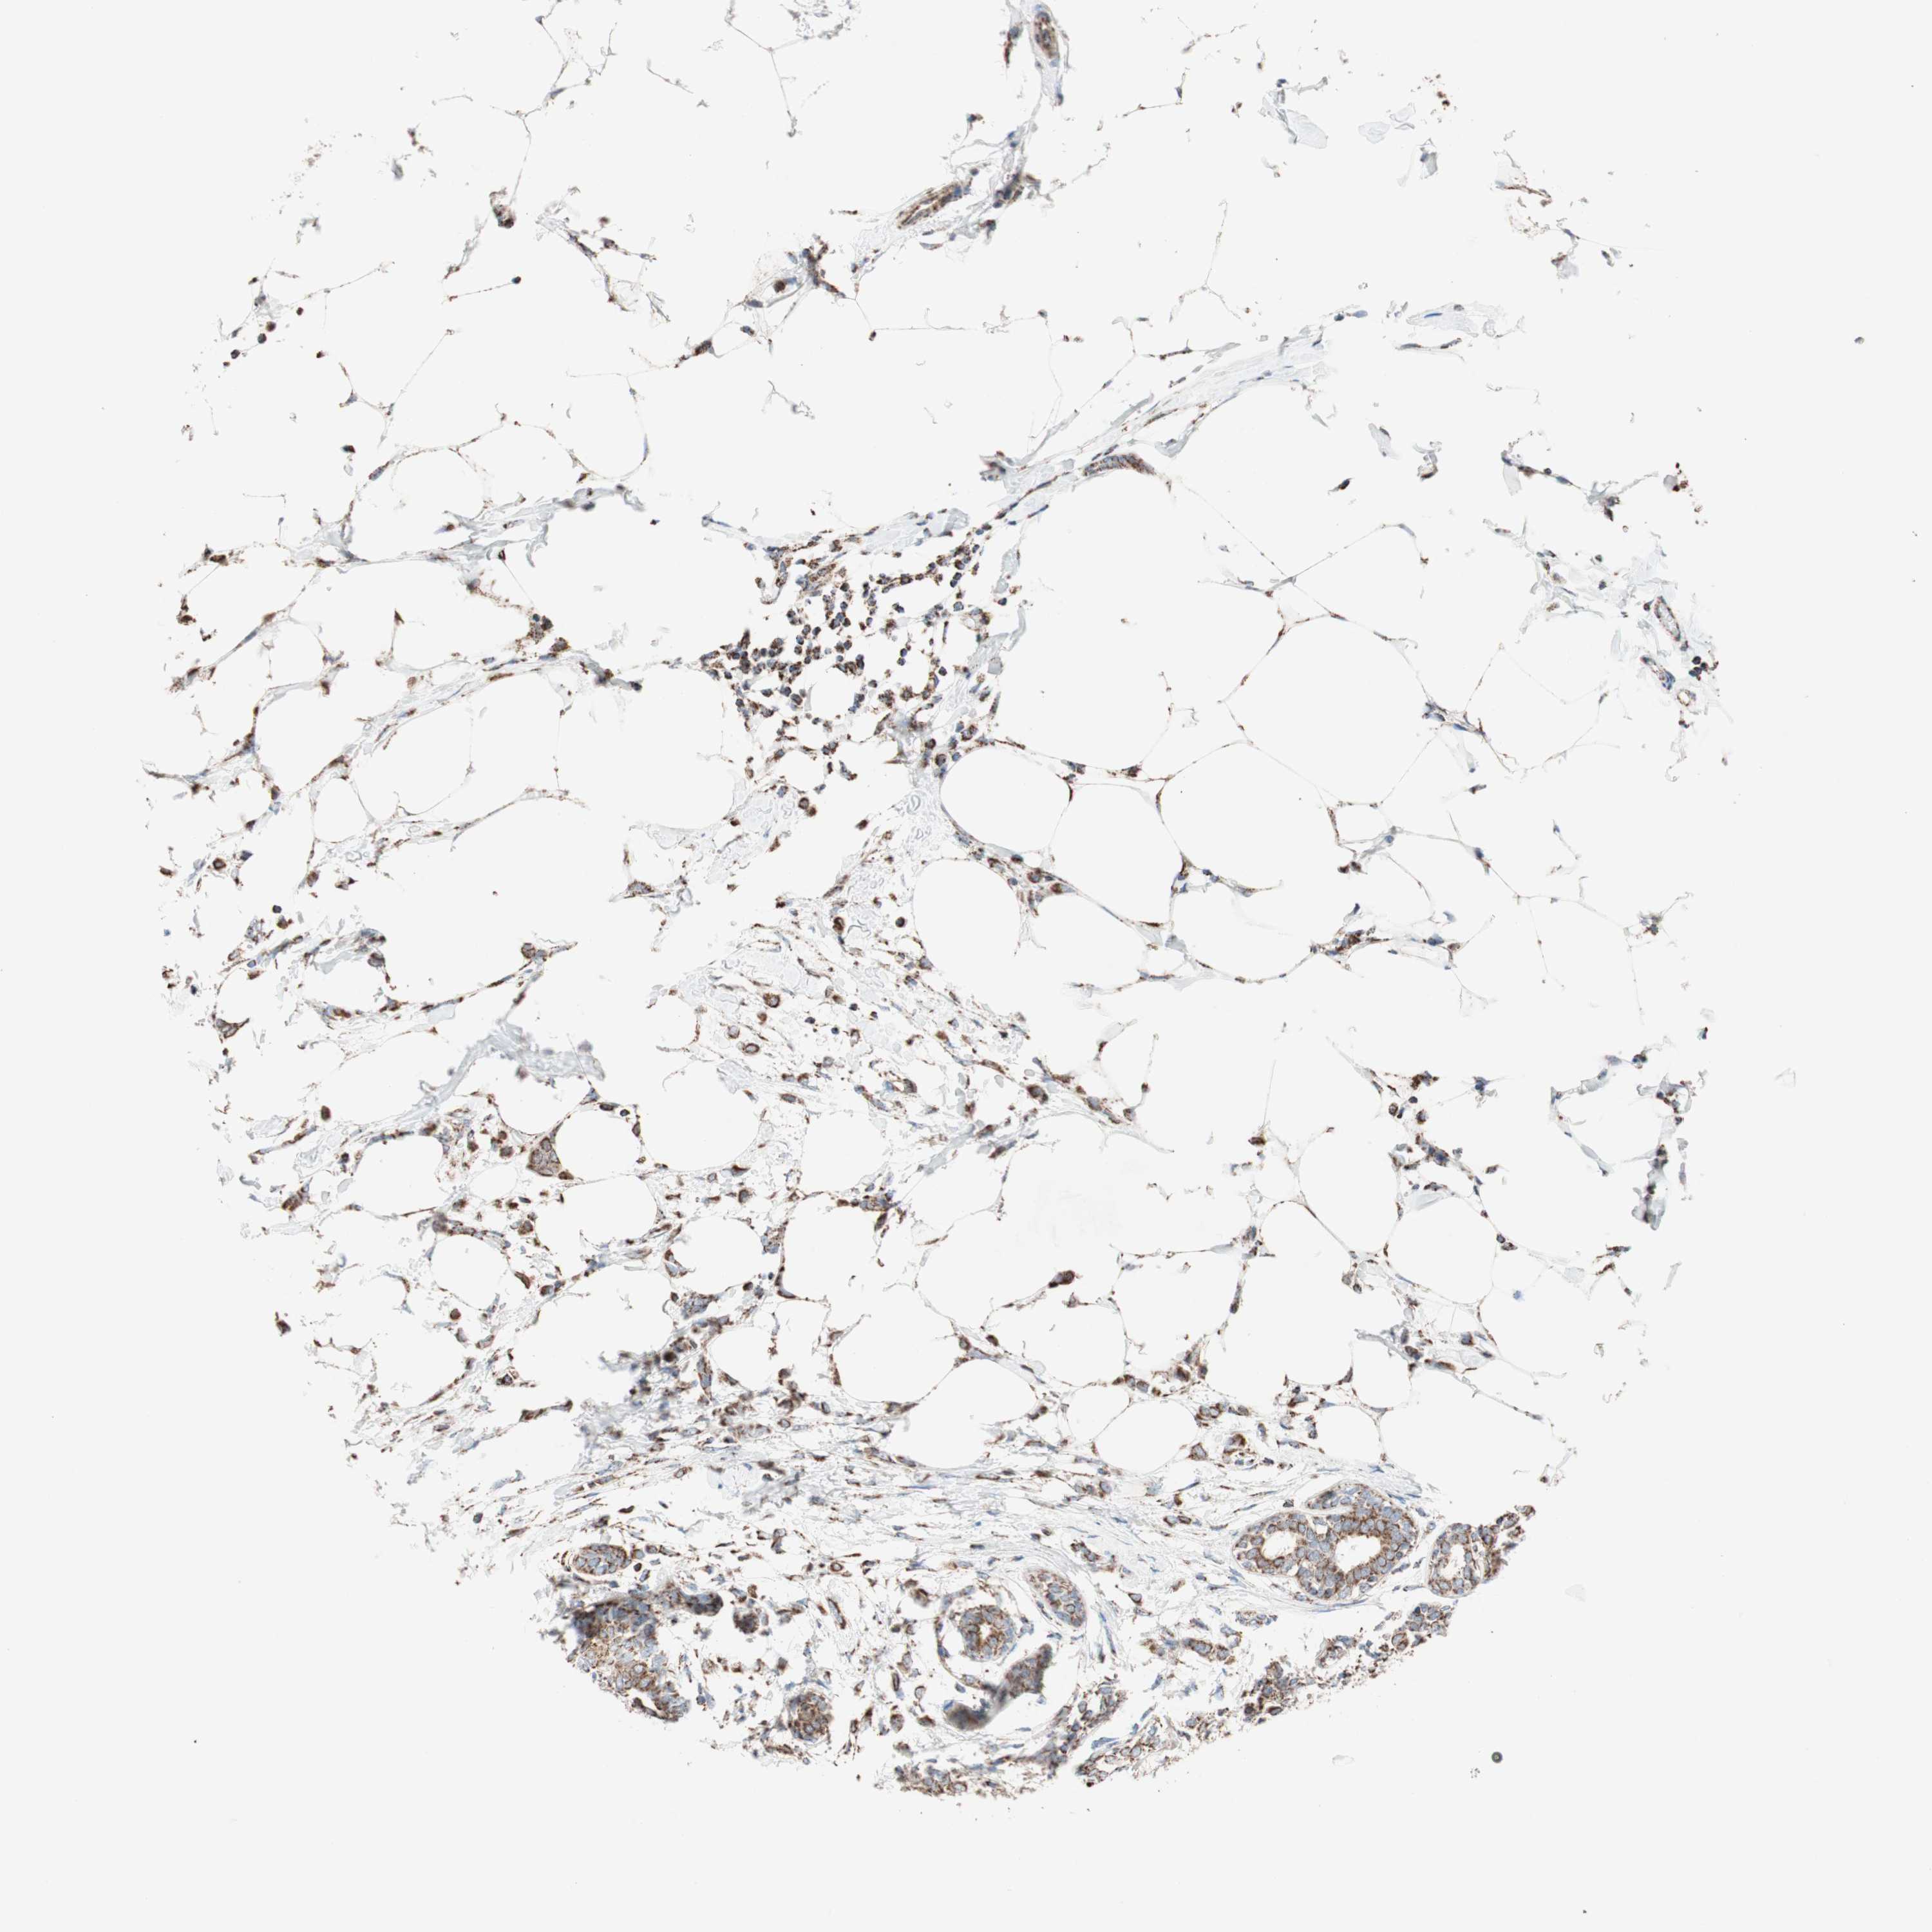

CANCER BREAST CANCER Show tissue menu

BRCA TCGA BRCA VALIDATION PROTEIN EXPRESSION